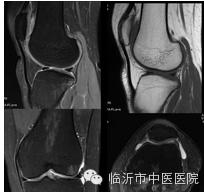

骨关节成像能更细致地观察膝关节半月板、韧带及滑囊的病变,做出准确的评估。

在早期关节软骨退变的诊断有一定的临床价值,可以提供客观、定量指标去检测骨性关节病的进展。